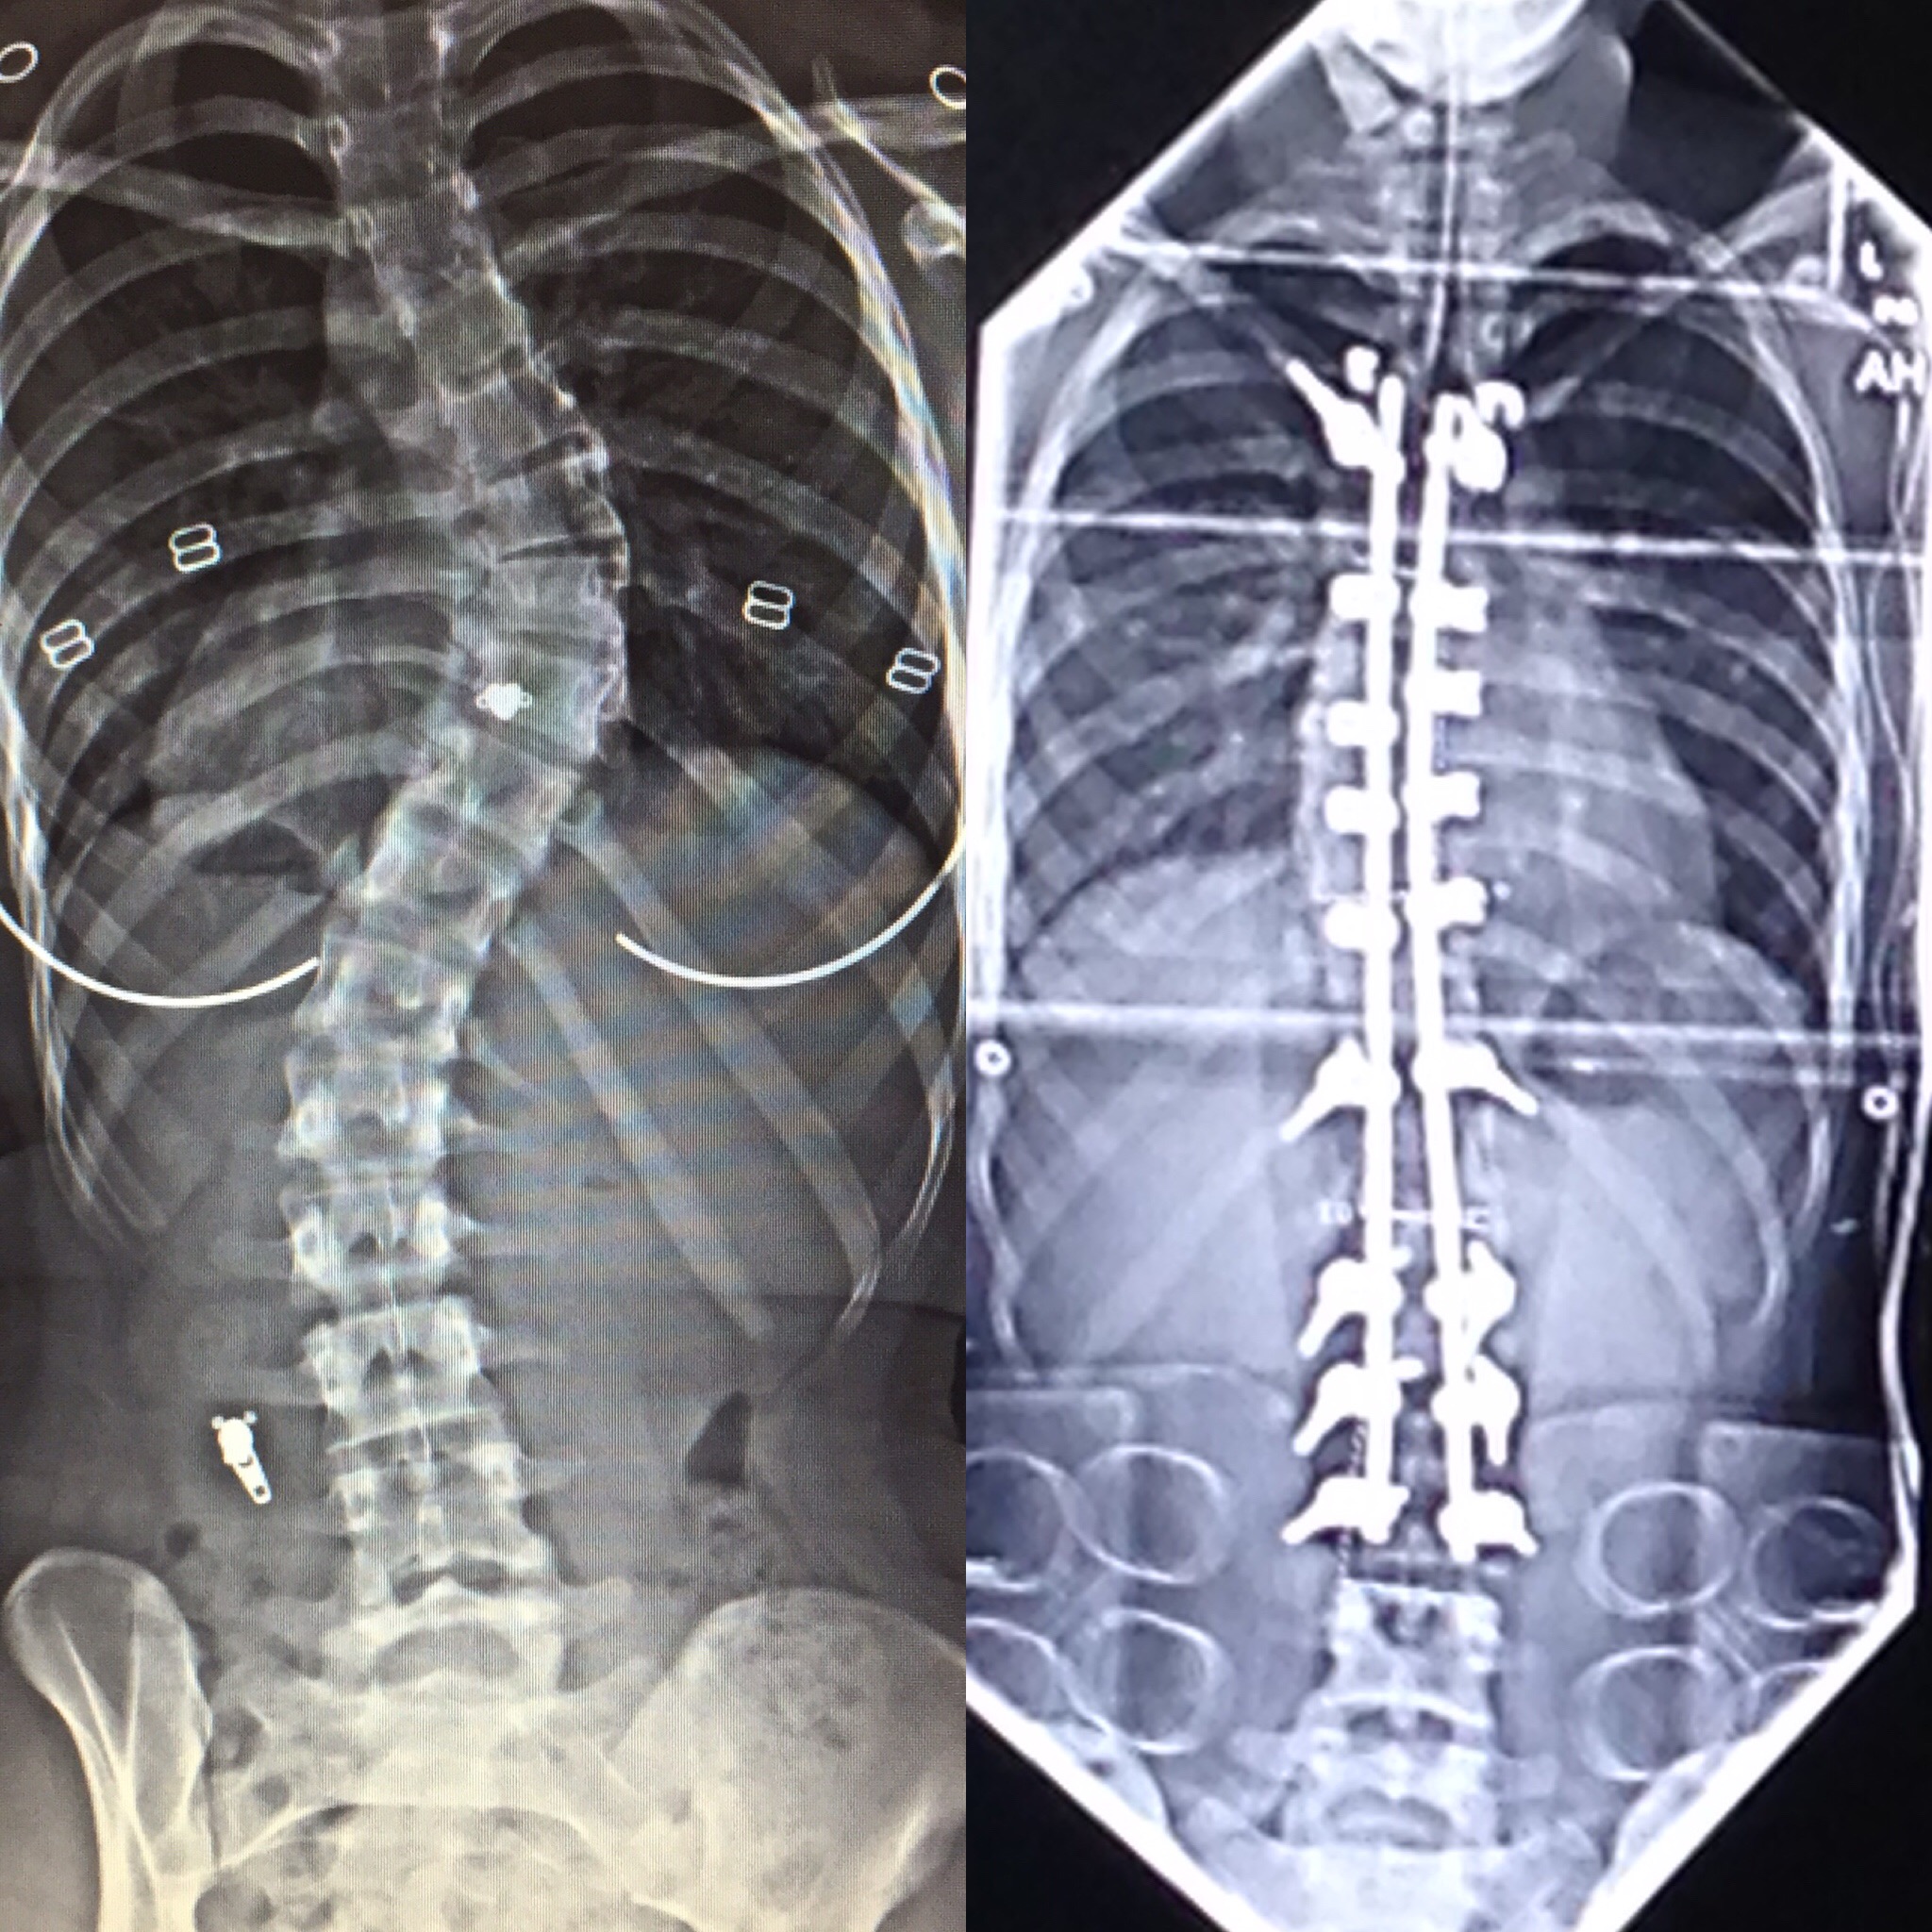

Измерение кифоза грудного отдела: Рентгеновские снимки